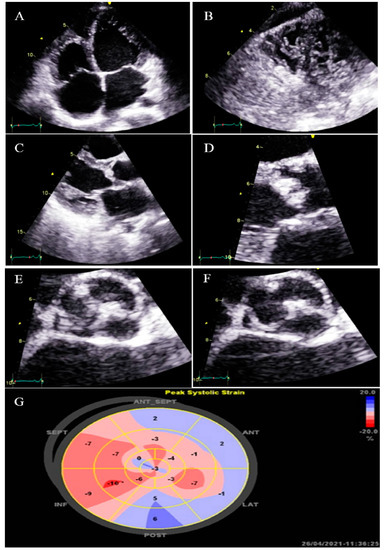

2.7. Case #7. BVNC, BAV, AS, and Dilated Aorta Ascending Aorta

A 48-year-old gentleman, a medical staffer, was referred to our clinic with dyspnea on moderate exercise and easy fatigability for 6 months, which had become worse over time. On cardiac auscultation, left- and right-sided S4 and S3 gallops, in addition to ejection systolic murmur grade III/VI in the aortic area, were audible. TTE showed non-compaction left and right ventricles with preserved biventricular systolic function, BAV, moderate AS, and dilated ascending aorta (diameter = 47 mm; indexed = 25 mm). At his request, he underwent diagnostic coronary angiography and left/right ventricular cineangiography, and the results showed patent epicardial coronaries plus hypertrabeculation of both ventricles in the biventricular cineangiography (Figure 7). A genetic study showed mutations in the MYH7 and MYBPC3 genes. The patient and the family members refused the genetic study because of the high costs of the test (not covered by the insurance). He denied undergoing CMR, due to claustrophobia, and was followed up medically (daily spironolactone 25 mg and carvedilol 6.25 mg twice per day). He was off pills 2 months later and did not return for further follow-up.

Figure 7.

Two-dimensional transthoracic echocardiographic views of case #7. (A,B); Biventricular non-compaction in apical four and three-chamber views. (C–F); Transesophageal echocardiography views, illustrating biventricular non-compaction in apical regions in addition to a thick, bicuspid aortic valve with restricted cusps motion (C,D), dilated ascending aorta (E), and increased transvalvular gradient in deep gastric view with a peak velocity of 3 m/s, in favor of moderate aortic stenosis (F). (G); Full volume three-dimensional transthoracic echocardiography, showing bicuspid, thick, and stenotic aortic valve (AVA by MPR = 1.4 cm2).